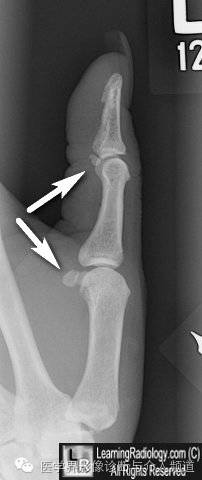

11、皮肤裂伤:皮肤裂口内空气的投影形似骨折,容易误诊。